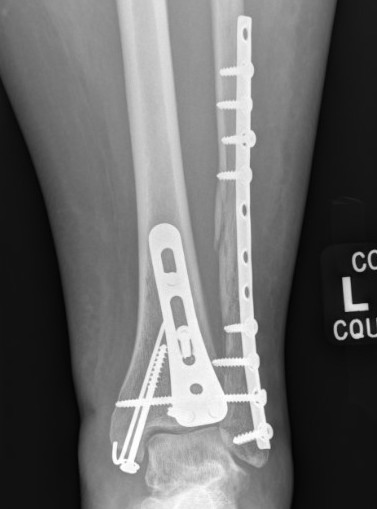

Tri-Malleolar Fracture

Lateral malleolus + medial malleolus + posterior malleolus

Posterolateral approach

- prone or lateral

- ORIF fibula + posterior malleolus

- move patient to supine to ORIF medial malleolus